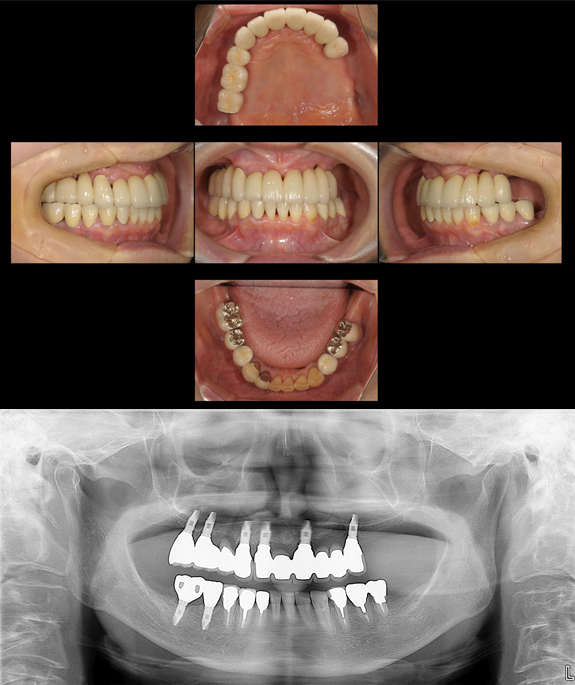

症例4

術前

準備中

術後